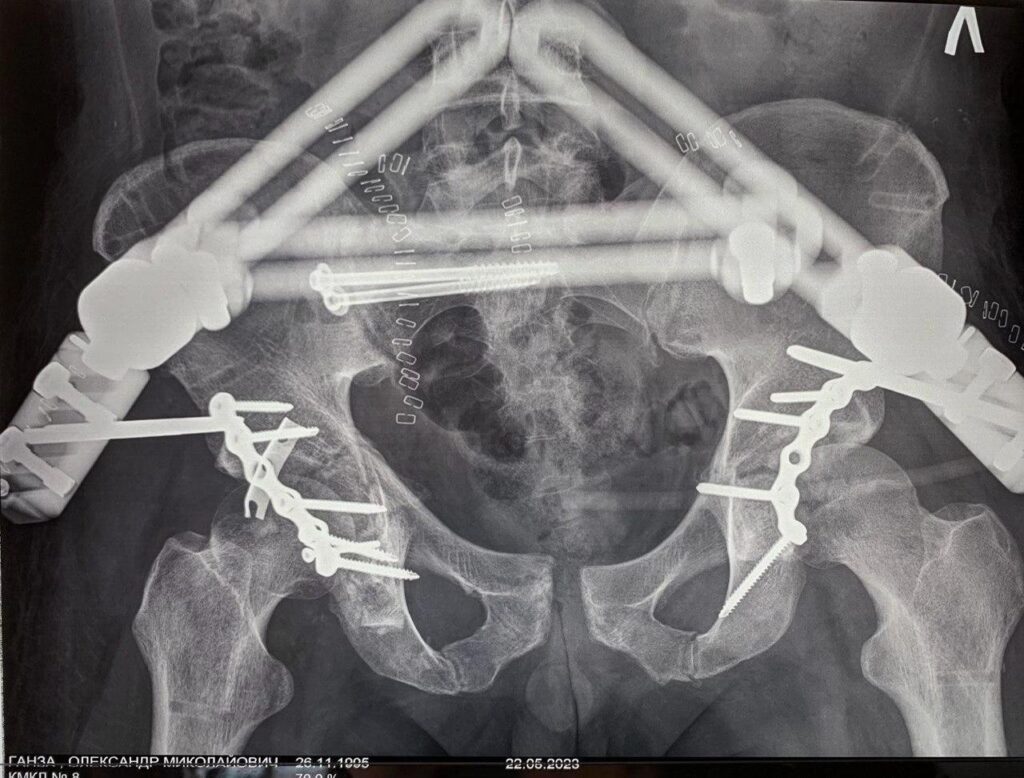

Наша лікарня є одним із небагатьох медичних центрів в Україні, де надають допомогу пацієнтам із важкими травмами та переломами кісток тазу ![]()

Такі травми потребують високої кваліфікації, сучасного обладнання та злагодженої роботи команди лікарів. У нашій лікарні застосовуються сучасні хірургічні методи, які дозволяють стабілізувати стан пацієнта, відновити функції та повернути його до активного життя ![]()

Ми беремося за випадки, які потребують особливої уваги та досвіду, і робимо все можливе для повноцінного відновлення пацієнтів ![]()